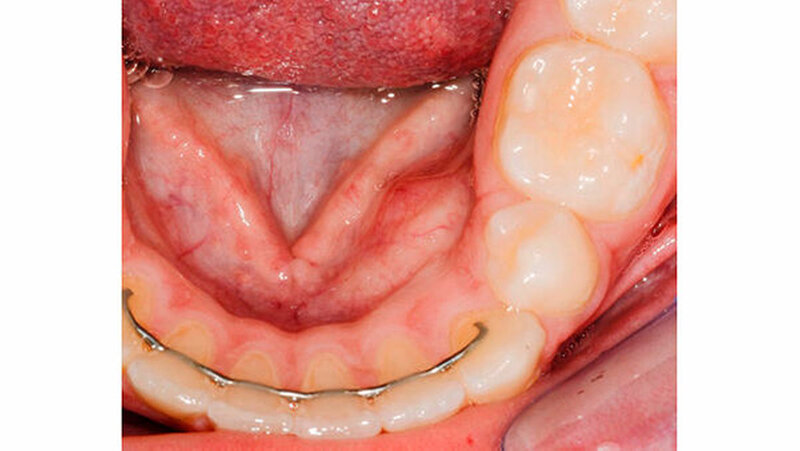

Auf Wunsch des Patienten wurde der operative Eingriff in Intubationsnarkose (ITN) durchgeführt. Nach der Einleitung der ITN sowie der üblichen Lagerung und Desinfektion des Patienten wurde lingual und bukkal von regio 41 bis regio 36 eine Terminalanästhesie (Ultracain D-S forte mit Adrenalin 1: 100.000, Sanofi-Aventis SA, Schweiz) gesetzt. Nach intrasulkulärer Inzision von regio 41 bis 36 lingual erfolgte die subperiostale Darstellung des Tumors (Abbildung 6). Nach Osteotomie der lingualen Kortikalis über dem Tumor wurde die Bindegewebskapsel eröffnet, und die hartgewebigen Tumoranteile konnten alle entfernt werden. Es folgte die vorsichtige Entfernung der gesamten Bindegewebskapsel (Abbildung 7).

Der Knochendefekt, der sich bis zu den Wurzeln der Zähne 33 und 34 ausdehnte, wurde nach gründlichem Ausspülen mittels physiologischer Kochsalzlösung mit einem Kollagenvlies (TissuFleece E 7×3 cm, Baxter Healthcare SA, Schweiz) gefüllt. Nach der Repositionierung des Mukoperiostallappens erfolgte der Primärverschluss mit interdentalen vertikalen Matratzennähten (Prolene 5-0, Ethicon, Fa. Johnson & Johnson, Norderstedt). Im Anschluss an den chirurgischen Eingriff wurde eine 0,1-prozentige Chlorhexidinspülung (Formula hospitalis, Zentrum für Spitalpharmazie, Luzerner Kantonsspital) dreimal täglich für zehn Tage verordnet.